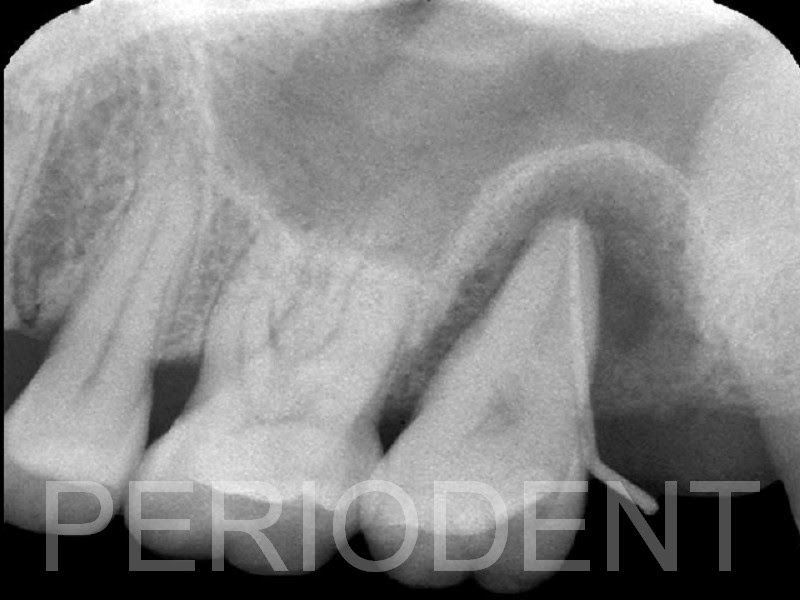

患者的左上第二大臼齒因為嚴重牙周病,需要拔除

患者不想做鼻竇補骨手術,所以拔牙時同時補骨以保存齒槽骨型態